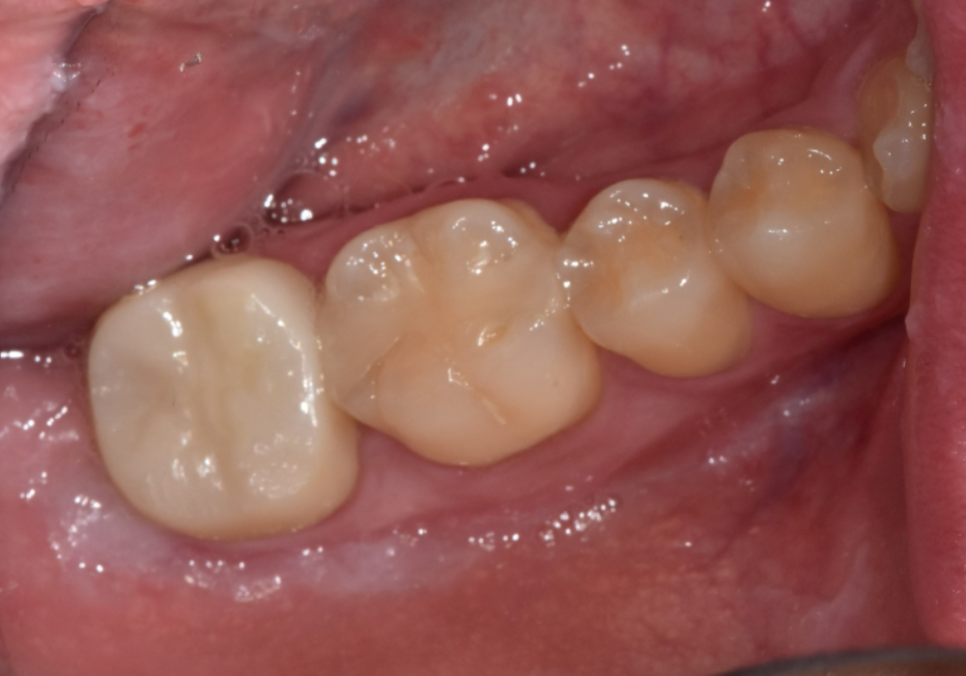

신경치료로 약해진 치아를 보호하기 위해

단단한 '지르코니아' 크라운을

예쁘게 씌워드렸습니다.

240228

어금니는 씹는 힘을 많이 받는 곳이라

지르코니아만큼 든든한 재료도 없답니다.

치료는 성공적으로 끝났지만,

환자분도 저도 약간의 아쉬움은 남았습니다.